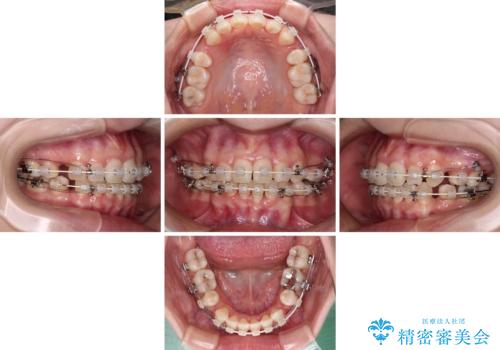

抜歯矯正へ切り替え 表側のワイヤー矯正

上下前歯が非接触である開咬は、インビザラインによる治療がお勧めではありますが、非抜歯矯正か抜歯矯正か悩む口元であり、途中抜歯矯正に切り替えたときに対応しやすいよう、ワイヤー装置にて治療を行うこととしました。

舌の突出癖の影響もあり、非抜歯矯正で治療開始したものの口元が突出し、唇が閉じにくくなってしまったため、途中で第一小臼歯4本を抜歯ししました。